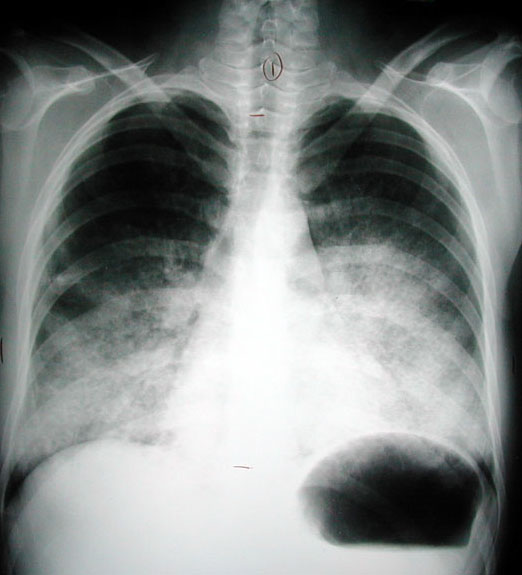

Lung Disease From Bats. These spores are found in soil and in the droppings of bats and birds. histoplasmosis (ohio valley fever) is an infection caused by a fungus. histoplasmosis is a disease caused by an infection with a fungus known as histoplasma capsulatum, which is common in the environment, most frequently in association with bird or bat droppings. histoplasmosis is a type of lung infection. The fungus lives in the soil. histoplasmosis is a type of fungal infection in your lungs. Some people also refer to the disease as cave disease. the infection can cause a lung disease similar to pneumonia in some people. You get it from breathing in the fungus histoplasma capsulatum (h. histoplasmosis is an infection caused by the fungus histoplasma capsulatum. The fungus spreads from bird and bat feces in the soil into the. histoplasmosis is an infection caused by the fungus histoplasma capsulatum. This fungus is found in soil, particularly around places where large amounts of bird. The lung infection is usually mild, but it can be more. It is caused by inhaling histoplasma capsulatum fungal spores.

Lung Disease From Bats histoplasmosis is an infection caused by the fungus histoplasma capsulatum. histoplasmosis is an infection caused by the fungus histoplasma capsulatum. These spores are found in soil and in the droppings of bats and birds. The fungus spreads from bird and bat feces in the soil into the. histoplasmosis (ohio valley fever) is an infection caused by a fungus. histoplasmosis is a type of lung infection. You get it from breathing in the fungus histoplasma capsulatum (h. It is caused by inhaling histoplasma capsulatum fungal spores. histoplasmosis is a disease caused by an infection with a fungus known as histoplasma capsulatum, which is common in the environment, most frequently in association with bird or bat droppings. This fungus is found in soil, particularly around places where large amounts of bird. histoplasmosis is a type of fungal infection in your lungs. The lung infection is usually mild, but it can be more. histoplasmosis is an infection caused by the fungus histoplasma capsulatum. Some people also refer to the disease as cave disease. the infection can cause a lung disease similar to pneumonia in some people. The fungus lives in the soil.